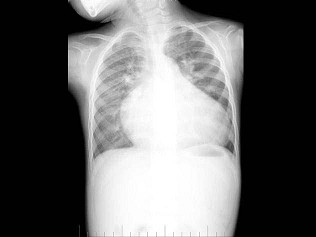

146、多项选择题

男,1岁零8个月,生长发育差,易患呼吸道感染,心悸气促,心脏正、侧位片检查如图所示,正确的描述和诊断是()

A.正位示心影向两侧扩大,心尖左移

B.肺纹理增多

C.侧位示心前间隙变窄,心后食管前三角间隙消失

D.房间隔缺损

E.室间隔缺损